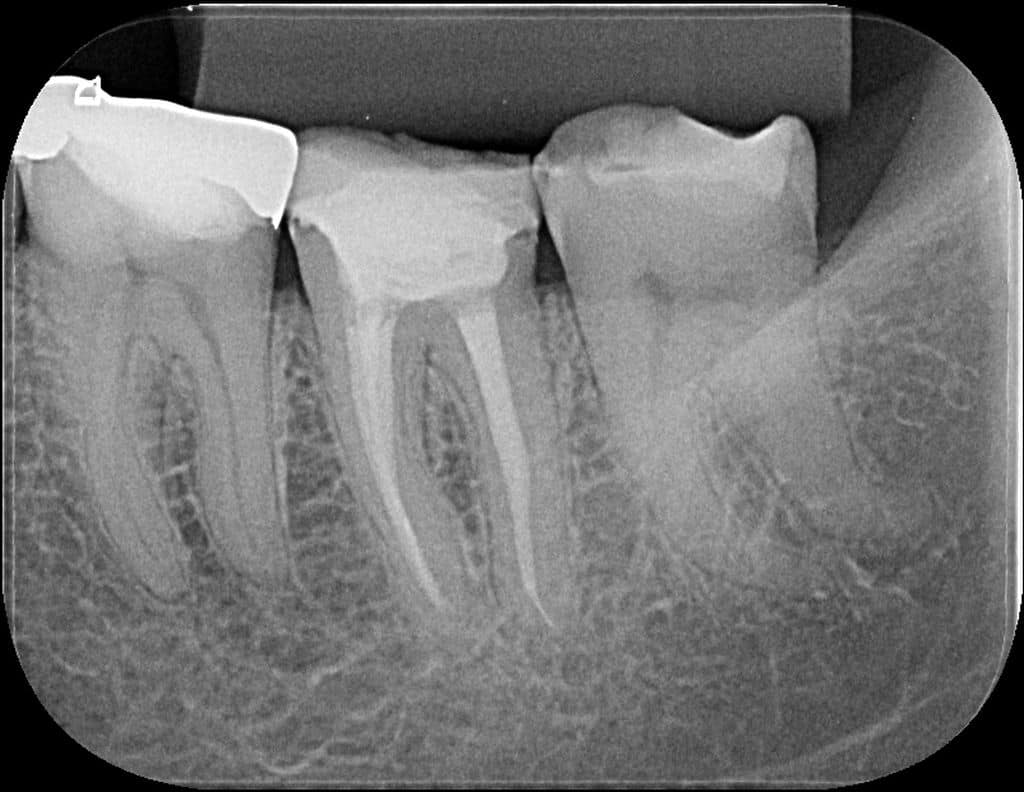

- Figura 1 – Radiografia inicial.

Paciente do gênero feminino, 56 anos de idade e caucasiana compareceu ao consultório se queixando de dor espontânea, pulsátil, que não cessava com o uso de analgésicos e anti-inflamatórios na região de mandíbula esquerda. Apresentou resposta negativa para o teste de palpação apical e percussão vertical e lateral em todos os dentes do referido quadrante. Aos testes térmicos apresentou resposta positiva exacerbada e de longa duração tanto ao frio quanto ao calor apenas no dente 37. Nos outros dentes do quadrante apresentou resposta positiva leve e de curta duração ao frio e negativa ao calor.

Segundo a classificação da Associação Americana de Endodontia, o dente 36 teve um diagnóstico pulpar e periapical de pulpite inflamatória irreversível com periápice normal. O tratamento indicado foi o tratamento endodôntico.